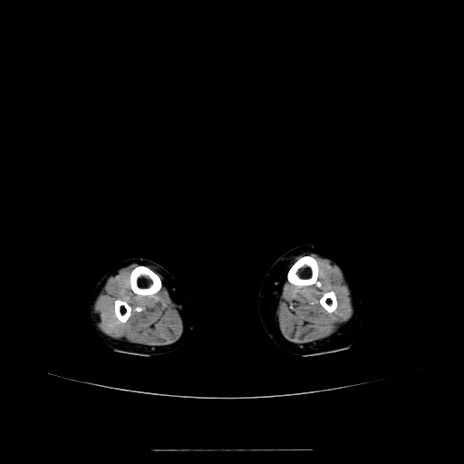

症例5(横断像)

【症例】70歳代女性

【主訴】お腹が張る

【現病歴】1週間くらい前から腹部膨満の自覚あり。昨日夜から増悪したため、本日救急外来受診。

【身体所見】意識清明、BT 36.5℃、BP 165/106mmHg、HR 80bpm、SpO2 98%、腹部:膨満、軟、自発痛・圧痛なし、触診にて不快感あり、腸蠕動音:減弱

【データ】WBC 12600、CRP 1.04